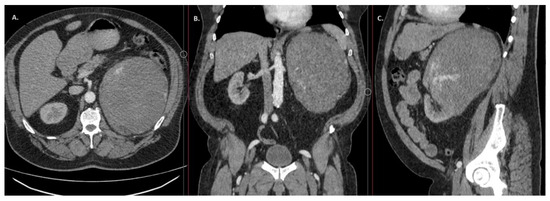

Introduction: Renal haemangioma is a benign tumour, and due to its characteristics, it must be distinguished from malignant diseases. We present a clinical case of primary renal angiosarcoma initially mistaken for haemangioma due to their similarity. Case report: A 58-year-old man was admitted to the hospital with suspicion of pulmonary embolism. The patient complained of pain on the left side. An ultrasound and CT scan of the abdomen showed a tumour mass ~20.5 × 17.2 × 15.4 cm in size in the projection of the left kidney. On CT images, there were data for clear cell renal clear cell carcinoma (ccRCC). A left nephrectomy was performed. However, histological examination revealed renal haemangioma. Three months later, the patient presented to the hospital with abdominal and lumbar pain. A CT scan showed multiple small hypoechoic foci up to 2 cm in size in the liver, lungs, and intra-abdominally, with the most data for carcinosis. Histological re-verification of the left kidney showed a renal vascular tumour with pronounced signs of infarction and necrosis with the majority of the evidence supporting angiosarcoma. Despite treatment, the patient’s outcome was fatal. Conclusions: Based on the clinical presentation, radiological images and histological examination data, the tumour was initially misdiagnosed as kidney haemangioma. Due to the rarity of this tumour, there are no established treatment protocols or clinical guidelines for managing primary kidney angiosarcoma. Full article

Anastomosing hemangioma (AH) is a rare subtype of primary vascular tumour that can, clinically and radiologically, present similarly to malignant renal tumours such as renal cell carcinoma (RCC) and angiosarcoma. Rarely seen in the genitourinary system, the ah we report here occurred in a 40-year-old male patient diagnosed initially with rcc based on imaging and successfully treated by laparoscopic left radical nephrectomy, with adrenal sparing and perihilar lymph node dissection. The pathologic diagnosis of ah can be challenging on small biopsy specimens; we therefore opine that it is appropriate to excise these lesions to facilitate diagnosis and definitively exclude common renal cancers. However, in this review, we describe some radiologic and pathologic distinctions between ah and malignant tumours. Full article